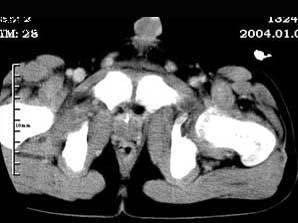

问题 女,35岁,7个月前无诱因出现左下肢阵发性疼痛,左骶髂部活动受限,进行性加重,排便困难,请根据所提供的图像,选择最佳选项 ( )

选项 A、转移瘤 B、滑膜肉瘤 C、软骨肉瘤 D、骨巨细胞瘤 E、脊索瘤

答案 B